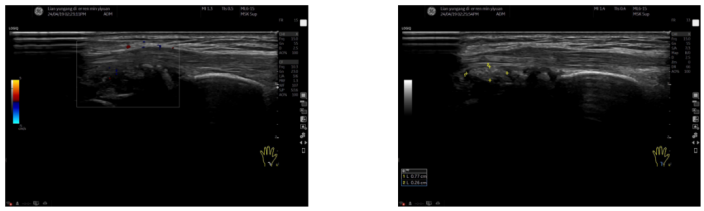

2024-03-13 右侧踝关节浅表超声:右侧踝关节内侧三角韧带及跟腱云雾状强回声(痛风石?);右侧踝关节内滑膜增厚伴痛风石形成(图2)。

图2. 右侧踝关节浅表超声2024-03-13 第一跖趾关节浅表超声:侧第一跖趾关节滑膜增厚伴痛风结晶形成;双侧第一跖趾关节内侧云雾状强回声(痛风石?);右侧第一跖趾关节积液;双侧第一跖趾关节可见骨侵蚀(图3)。

图3. 第一跖趾关节浅表超声2024-04-18 左侧腕关节浅表超声:左侧腕关节滑膜增厚伴痛风石形成;左侧腕关节少量积液(图4)。

图4. 左侧腕关节浅表超声2025-01-21 右膝关节浅表超声:右侧膝关节积液;右侧膝关节滑膜炎伴痛风石形成,可见骨侵蚀;右侧股四头肌腱内强回声(痛风石?);右小腿软组织水肿(图5)。